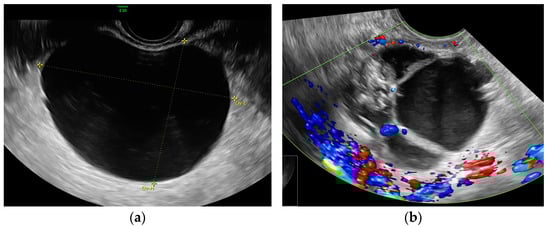

- Simple cysts—Unilocular, anechoic cysts with smooth walls and no papillary projections.

- Complex cysts—Cystic lesions with additional features such as septations, solid components, internal echogenicity, or vascularity.